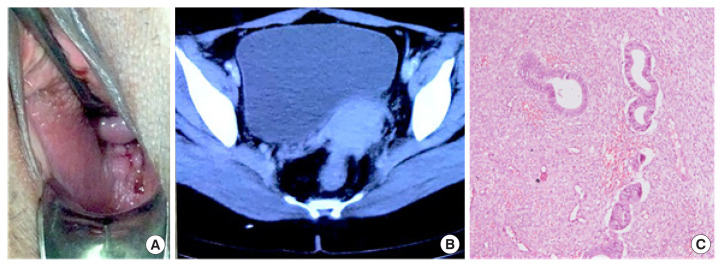

Extrauterine endometrial stromal sarcoma arising from malignant transformation of the vagina is an extremely rare condition. The diagnosis is often difficult as the symptomatology and pathological features overlap with that of pelvic endometriosis. A 38 years old female presented with complaints of dyspareunia, dysmenorrhea, and painful defecation along with blood-stained vaginal discharge for a year. Examination revealed the presence of multiple brownish irregular nodules in posterior vaginal fornix and fixed tender nodules which on biopsy revealed florid vaginal endometriosis. She improved symptomatically on medical therapy. After 18 months of diagnosis, she presented again with a necrotic growth in posterior fornix, which on repeat biopsy revealed a low-grade endometrial stromal sarcoma. Laparotomy revealed a 7×5 cm mass in the pouch of Douglas, infiltrating the posterior vaginal wall and rectum. A complete cytoreductive surgery with retrograde hysterectomy, excision of posterior vaginal wall and rectosigmoid resection was done. The patient is disease-free at a follow-up of 65 months.